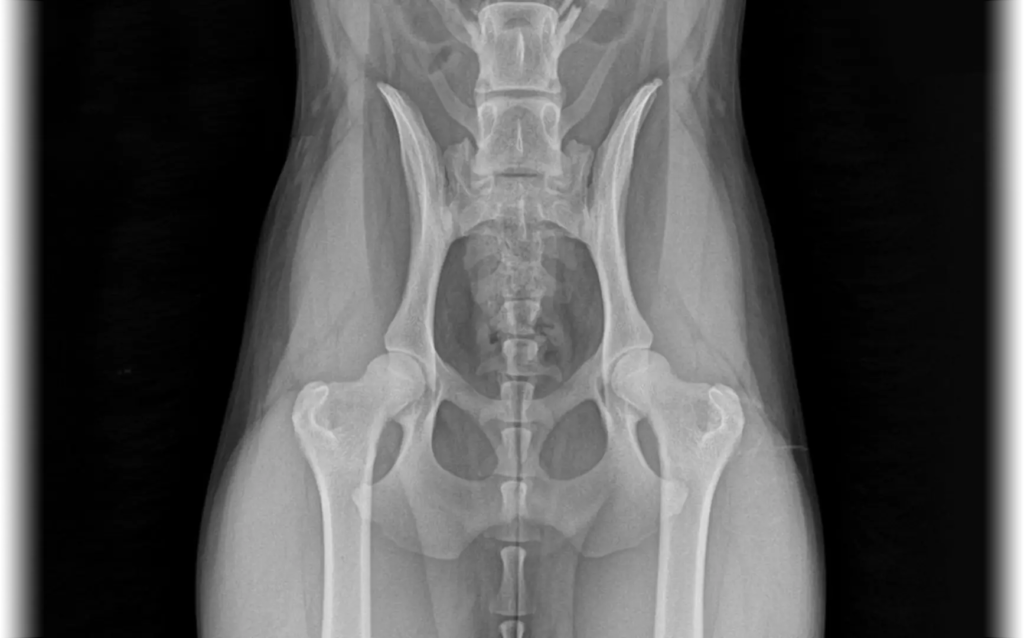

Health Testing and Best Practices

MASCUSA is committed to supporting the long-term health and preservation of the breed. We stay informed on emerging research, health statistics, and genetic discoveries, and work closely with laboratories and researchers to identify potential concerns. By monitoring trends and collaborating with experts, we are able to make informed recommendations on essential health testing and responsible breeding practices.

Whether you are a breeder, competitor, or devoted owner, understanding recommended health screenings helps protect the future of the Miniature American Shepherd.